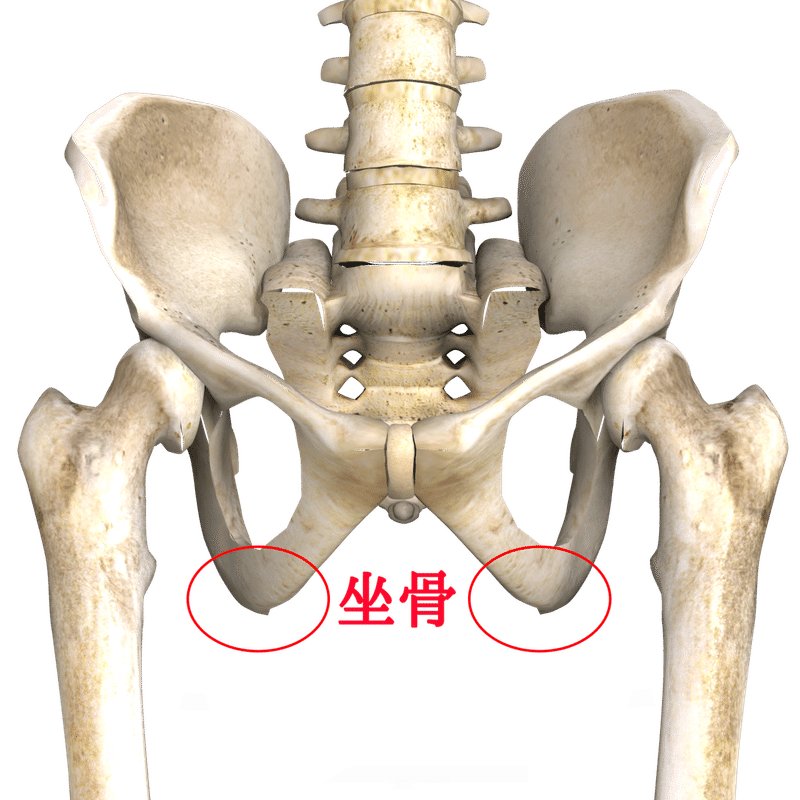

あぐらをかいて座る女性 写真素材フォトライブラリーは、日本のストックフォトサイトです。ロイヤリティーフリー画像を販売。動画素材はsサイズすべて無料。 s550円~ id: あぐらをかいて座る女性 はこちら縁側であぐらをかく和服姿の男性 の写真素材・イラスト素材|アマナイメージズ 縁側であぐらをかく和服姿の男性 の写真素材・イラスト素材。 アマナイメージズでは3000万点以上の高品質な写真素材・イラスト素材・動画素材が購入可能です。 ロイヤリティフリー作品だけでなくライツマネージド作品も豊富に取り揃えています。 椎間板ヘルニアが原因で、あぐらをかいて足がしびれる? あぐらの姿勢は通常、 椎間板ヘルニア の症状が楽になる姿勢なので可能性はとても低いと考えられます。ヘルニアで神経が圧迫されているためにしびれが出ているなら、日常生活のいろいろな場面でしびれや痛みを感じているは

くことにより吸収され、 弱められる。あぐら姿勢で手を膝に置く場合、肘 関節が90度程度に屈曲する。このためあぐらでは、肘関節が身体の揺 れに合わせて動きやすく、呼吸などによる揺れを相殺する働きをしたの ではないかと思われる。あぐらをかいた時に、脚が床につかず、浮いてしまう。両手で膝を押し下げようと頑張っても、脚に力が入り、曲がらない。 あぐらをかいた時、脚が浮いてしまう?/photo by Kentaro Abe 股関節が硬いタイプが苦手なポーズ 股関節が硬い人が苦手なポーズ唱題の姿勢|願い方次第で必ず叶う勤行・題目 について 朝晩の勤行の時に、まず真剣に願いをかけるのです。 自分が願いたいことを順番に紙に書いて、勤行の後の題目の時に、一つずつ自分の生命に叩きこむように真剣に願うのです。 例えて言うなら

胡坐 あぐら と腰痛の関係 スポルト鍼灸整骨院 中野店 スポルト鍼灸整骨院 中野店

胡坐 あぐら と腰痛の関係 スポルト鍼灸整骨院 中野店 スポルト鍼灸整骨院 中野店

胡坐 あぐら と腰痛の関係 スポルト鍼灸整骨院 中野店 スポルト鍼灸整骨院 中野店